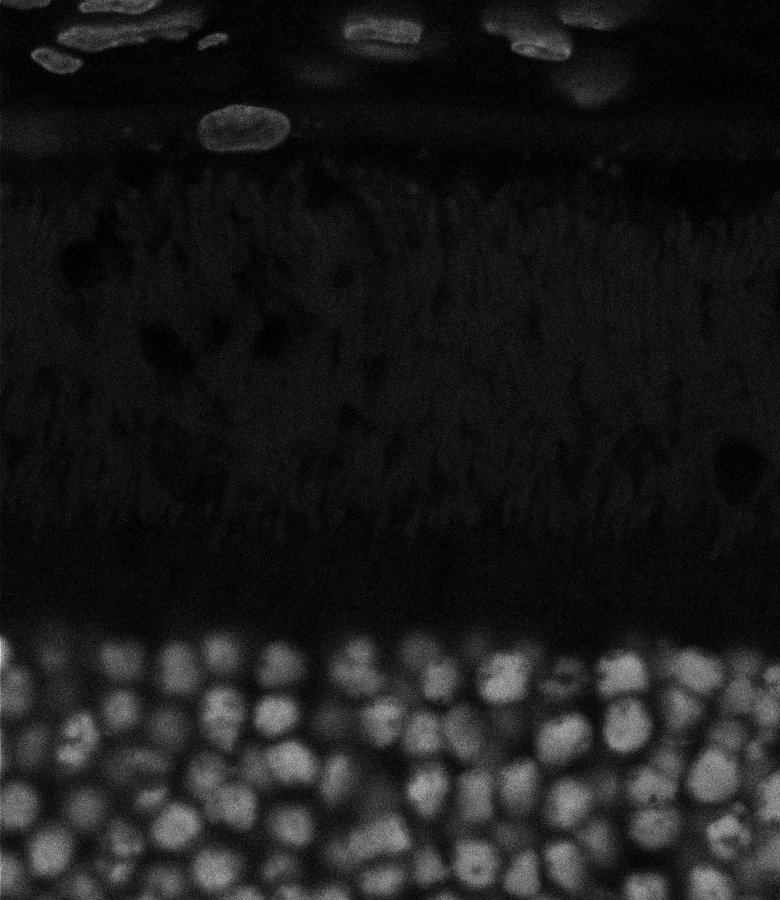

Unhealthy Choroid